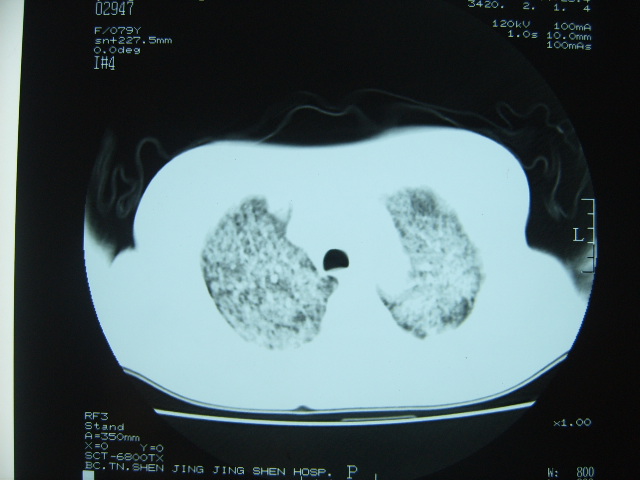

标题: CT7574:双肺病变,请会诊。急!急!

女 79岁,今日高烧,无咳嗽及痰,是否粟粒结核还是?

双肺弥漫性病变,以肺间质改变为主,

胸内小结节部分融合成片,边缘模糊,

双肺弥漫小结节状高密度,部分融合,边界不清(因为不是hrct,可能为部分容积效应引起),肺门纵隔内未见肿大淋巴结影。无胸腔积液。

考虑:急性血型播散型肺结核,不除外过敏性肺炎;建议治疗后复查。

双肺弥漫性结节影,双肺上叶为著.纵隔内可见一肿大淋巴结影,密度较高.支持急性血行播散型肺结核.双侧少量胸腔积液.

双肺弥漫基本均匀分布的小结节状高密度影,部分融合。支持急性血性播散性肺结核。

两肺弥漫分布小结节状高密度影,其大小,密度一致,分布均匀,并可见与后胸壁平行的弧状影

诊断:两肺急性血型播散形肺结核